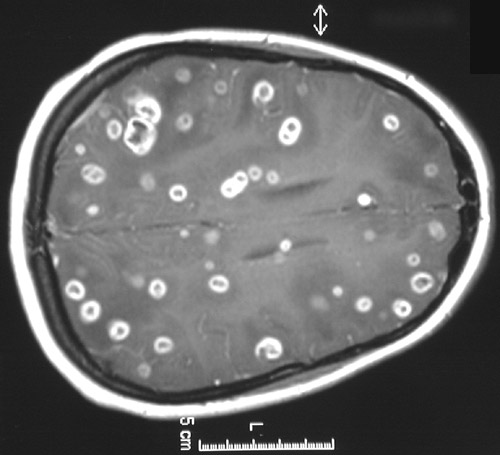

![]() | These T1 weighted MRI scans with gadolinium enhancement reveal numerous brightly enhancing ring enhancing abscesses in axial view above and coronal view below. This patient was immunocompromised and had a chronic lung abscess. Long filamentous organisms faintly acid fast were recovered on bronchoalveolar lavage of the lung, and Nocardia asteroides was cultured. |